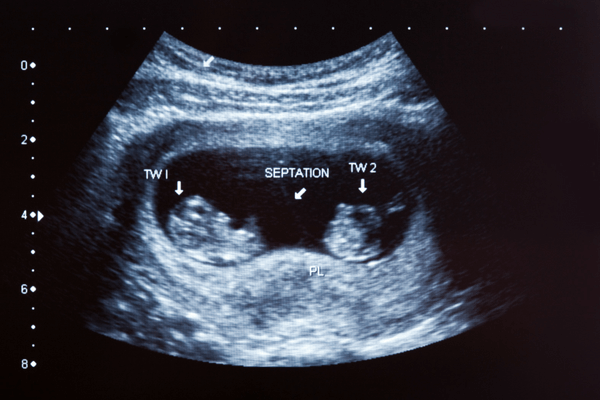

Ultrasound Level 2 (Twin Pregnancy)

Ultrasound Level 2 (Twin Pregnancy) is a specialized imaging procedure tailored for pregnancies involving twins or multiples. Conducted typically between 18 to 22 weeks of gestation, this comprehensive scan provides detailed assessments of the fetal anatomy, growth, and development of each individual fetus. With twins, it’s particularly important to evaluate factors such as the placental location, amniotic fluid levels, and any signs of twin-to-twin transfusion syndrome (TTTS) or other complications unique to multiple pregnancies. The Level 2 ultrasound for twin pregnancies helps healthcare providers identify any structural abnormalities, assess the chorionicity (whether the twins share a placenta), and guide management decisions to ensure the optimal health and well-being of both fetuses and the expectant mother throughout the pregnancy.